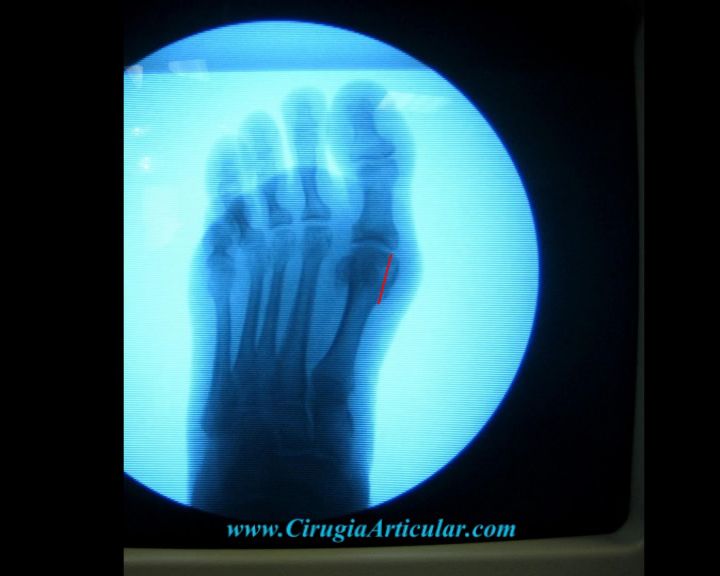

Foto 20

Vemos en la radiografía el resultado final de la cirugía. Vemos como hemos obtenido una alineación perfecta del primer dedo con respecto al pie (línea roja).